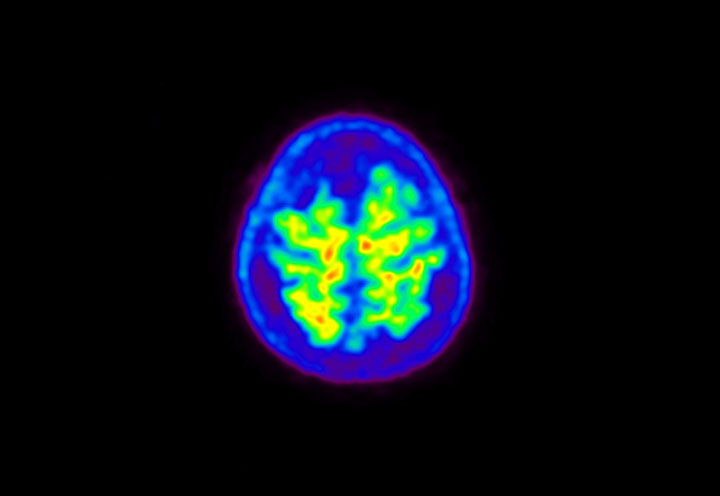

Head / Case5 : Amyloid

Axial

Courtesy : Kindai University Hospital

- Imaging protocol

- Injected dose: 4.27 MBq/kg, 18F-Flutemetamol

- Uptake time: 99 minutes

- Scan time: 20 minutes